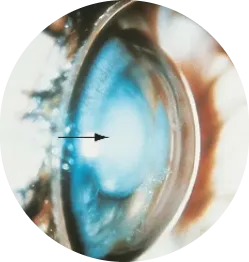

Secondary Glaucoma

Secondary glaucoma develops as a result of another underlying condition that affects the eye. It may be triggered by eye injuries, inflammation, diabetes, certain medications like steroids, or previous eye surgeries. This type of glaucoma can appear in either open-angle or angle-closure forms. Since it’s linked to other health issues, managing the primary cause is essential to control the pressure. Prompt treatment helps prevent further optic nerve damage and vision loss.

Glaucoma drainage devices for recalcitrant glaucoma especially neovascular glaucoma’s which are not amenable to medical therapy.

Glaucoma drainage devices for recalcitrant glaucoma especially neovascular glaucoma which are not amendable to medial therapy.